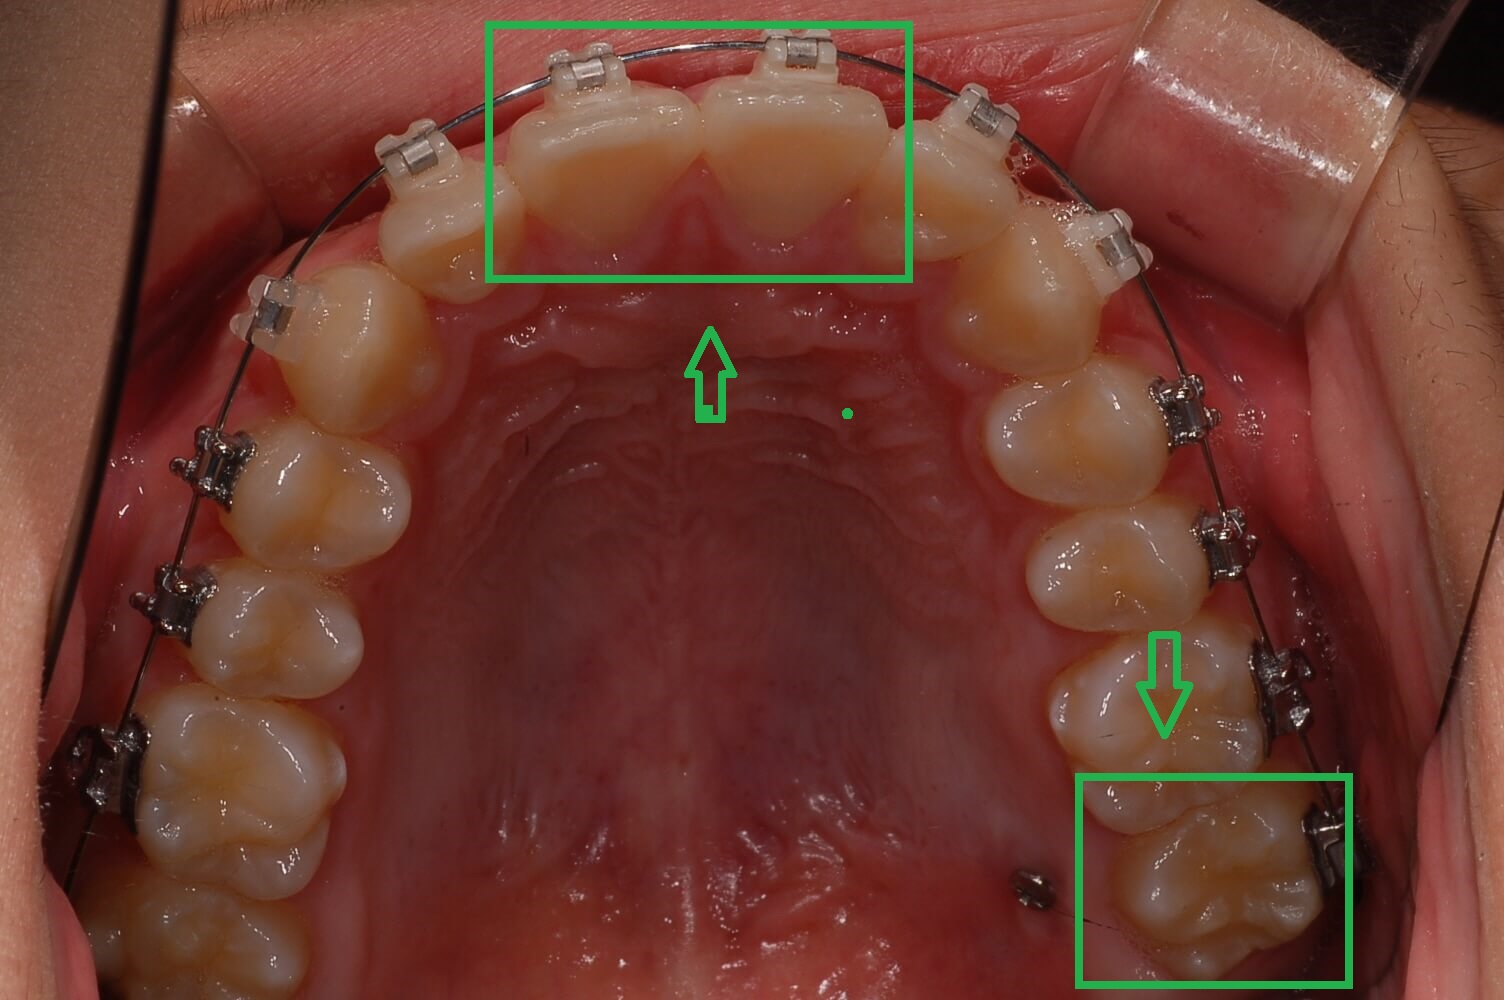

▼ 3개월 후 어금니 가위교합 교정상태(아래 어금니)

▼ 3개월후 어금니 가위교합 교정상태(윗 어금니)

2. 가위교합 교정실시 (3개월 상태)

사진을 보시면 거의 정상으로 돌아왔습니다. 사실 이때 이 정도면 그냥 살아도 되지 않나 하는 생각도 해보았습니다.

하지만 이 상태로 두면 치아는 복원력이 강해 다시 누울 수 있고 어금니가 일어섬으로써 다른 치아들과 맞물리는 높이가 맞지 않아 더 큰 문제 발생된다는 것을 알았습니다.

윗 어금니는 생각보다 제자리에 돌아오는 속도가 늦었으나 전체 블라켓을 설치하고 과개교합 교정에 들어갔습니다.